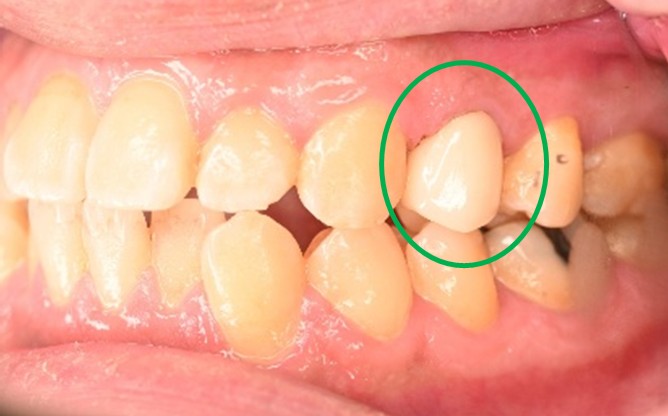

女性 Sさん 50代 (オールセラミック冠)

主訴

左上の差し歯がとれたままになっている。

治療内容

レントゲンを撮り詳しく診てみると、歯根が破折して保存することができず、抜歯する必要があることがわかりました。抜歯後、オールセラミックブリッジで補綴(欠損した部分を人工物で補う)しました。ブリッジの支台になっている後方の歯は、根尖性歯周炎(根の先端で問題を起こしている)でしたので、根管治療をしています。

所感

抜歯後、欠損部分を補う方法には、1本だけの部分入れ歯、ブリッジ、インプラントの3つの方法があります。この患者さんは、ブリッジを選択されました。メタルフリーの治療を希望されましたので、土台をファイバーコアにし、オールセラミックのブリッジをかぶせました。患者さんは、お口の中の金属を徐々に減らしていきたいということです。体全体の健康のことを考えると正しいことです。

オールセラミック冠(失活歯)1本:¥104,500(税込)

オールセラミック冠(生活歯)1本:¥93,500(税込)

ポンティック1本:¥93,500(税込)

合計:¥291,500(税込)